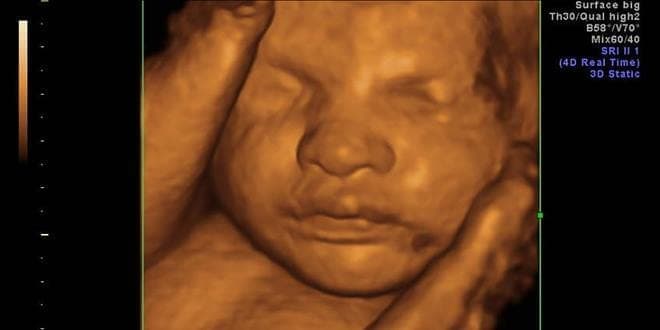

Ο υπέρηχος 4D, δίνει τρισδιάστατη εικόνα του μωρού σας.